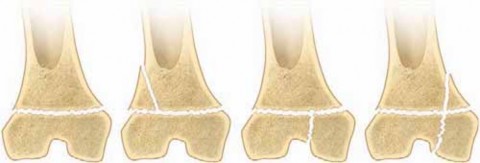

Chapter 15 Distal Femoral Physeal Fractures R. Dale Blasier DEFINITION Distal femoral physeal fractures invol…